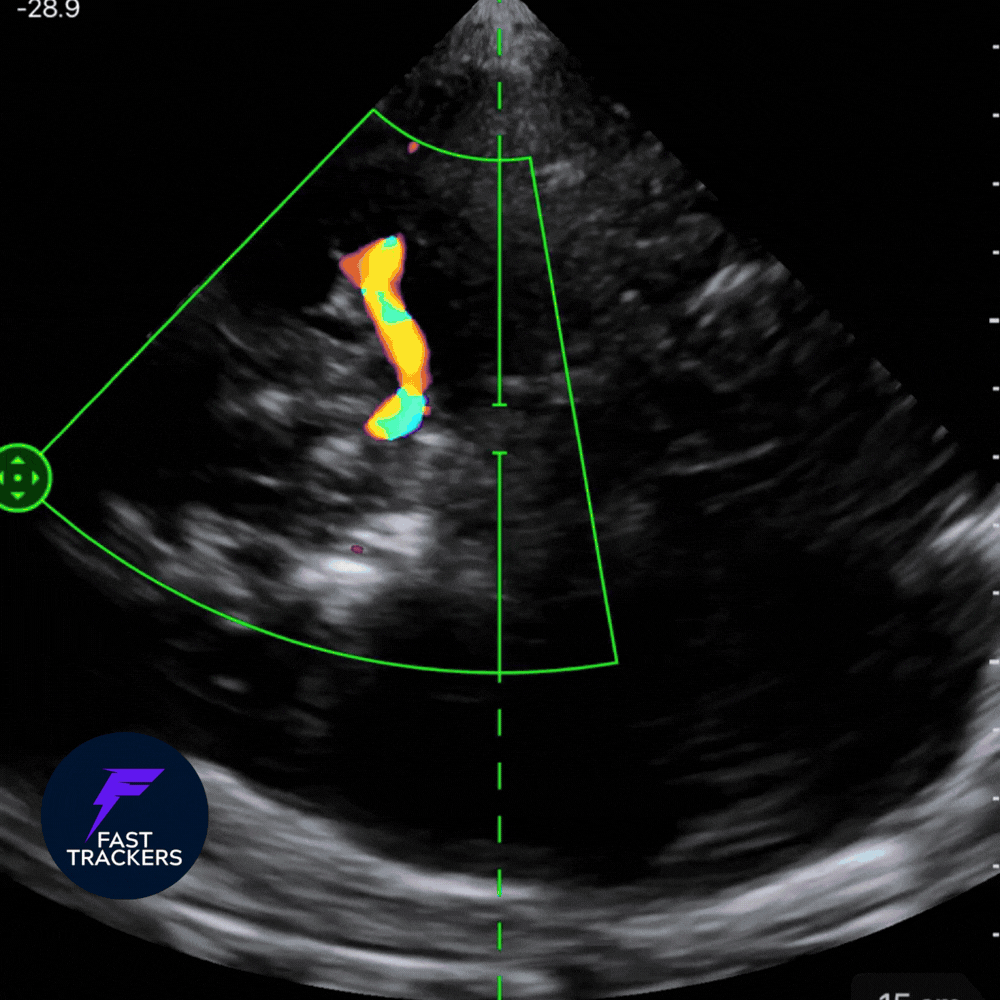

2️⃣ Activation du Doppler couleur

-

Activer le Doppler couleur.

Chercher un flux latéral au tronc cérébral.

Ajuster le gain pour éviter le bruit.

Une fois le flux identifié ➡️ Réduire la profondeur pour centrer l’écran sur l’ACM.